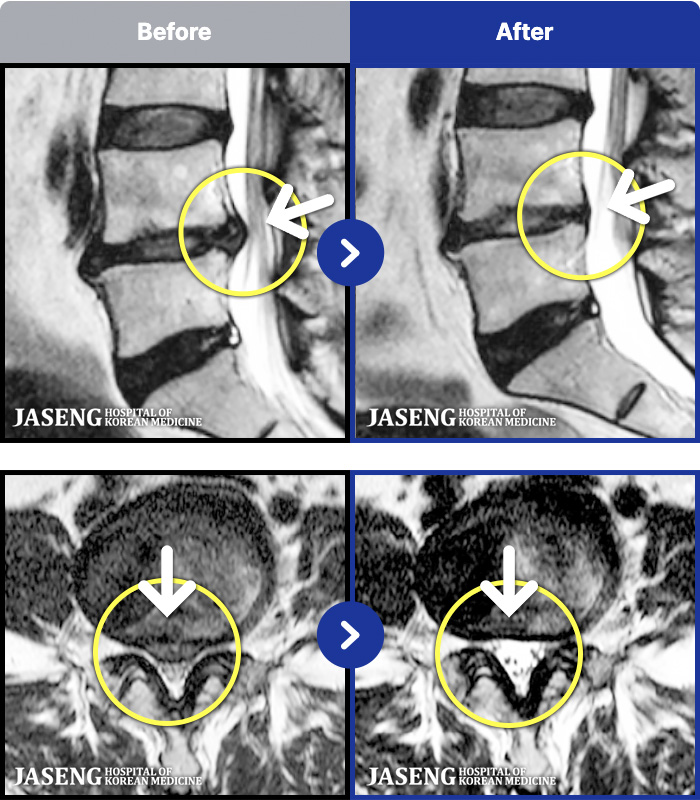

[뱸] 19.11.28~25.05.06

ȯںп Ǹ ǿ ԿǾ, ο ġ ۿ Ƿ ġḦ Ͻñ ٶϴ.